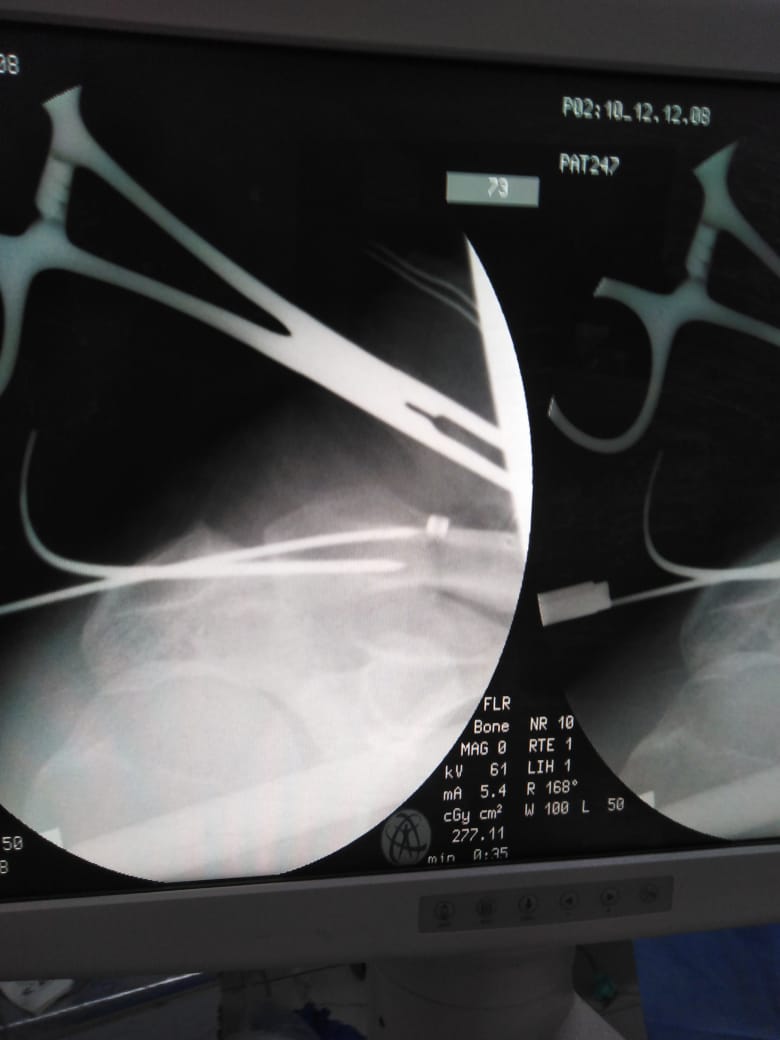

بتقنية جديدة.. نجاح أول عملية تثبيت خلع بمفصل الكتف في "دكرنس العام"

أعلن الدكتور سعد مكي وكيل وزارة الصحة بالدقهلية عن نجاح فريق طبي بإجراء أول عملية تثبيت خلع بمفصل الكتف بتقنية جديدة بمستشفى دكرنس العام لمريض يبلغ من العمر 40 عامًا.

الفريق الطبي، الدكتور خيري كامل رئيس قسم العظام، الدكتور أحمد عبد القادر استشاري العظام، الدكتور عيد حسن أخصائي العظام، الدكتور عصام حمدي استشاري التخدير.